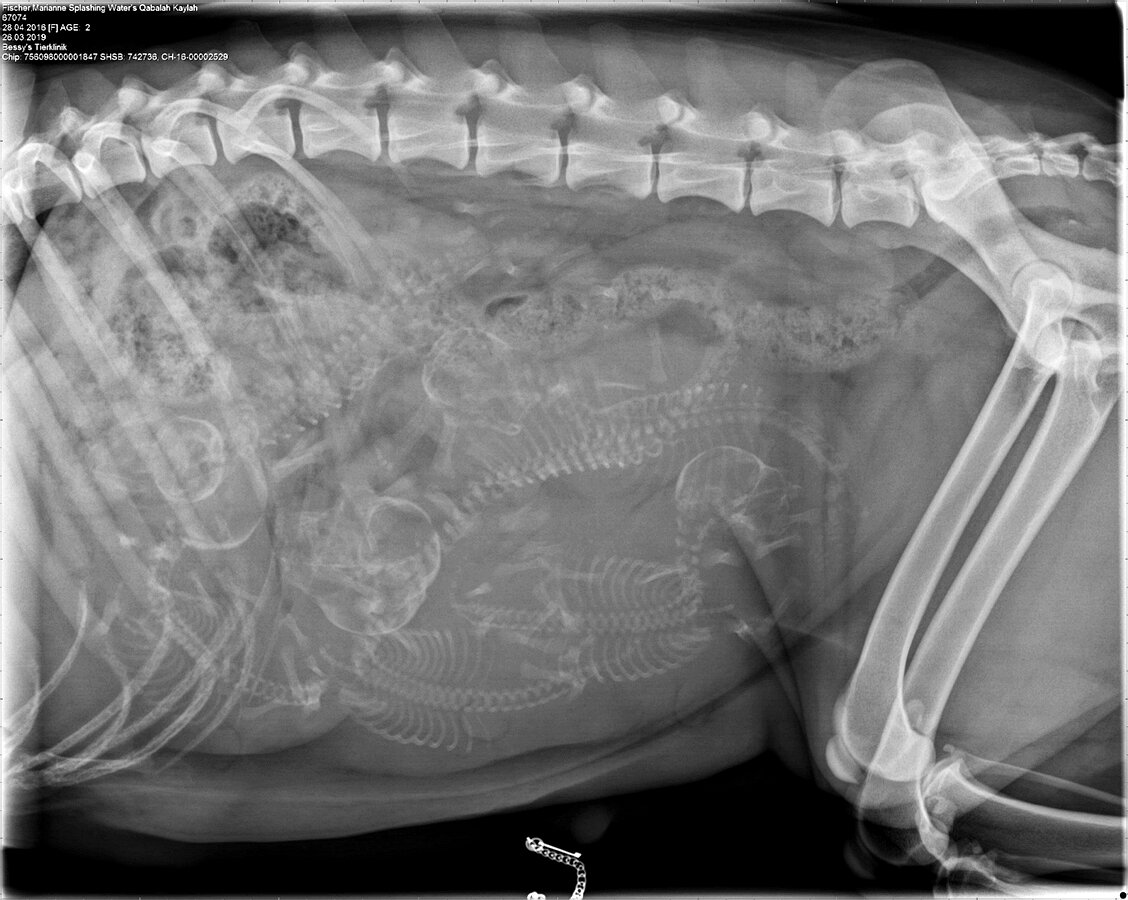

Auf dem Röntgenbild konnten wir klar 6 kleine Skelette zählen. Nun heisst es noch knapp eine Woche Geduld haben, bis die Welpen da sind!